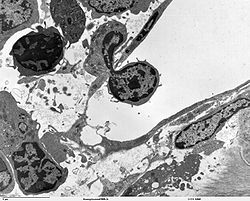

As new research techniques, such as electron microscopy, immunohistochemistry, and molecular biology have expanded the means by which biomedical scientists can study disease, the definition and boundaries of investigative pathology have become less distinct. In the broadest sense, nearly all research which links manifestations of disease to identifiable processes in cells, tissues, or organs can be considered experimental pathology.

Anatomical pathologists diagnose disease and gain other clinically significant information through the examination of tissues and cells. This generally involves gross and microscopic visual examination of tissues, with special stains and immunohistochemistry employed to visualize specific proteins and other substances in and around cells. More recently, anatomical pathologists have begun to employ molecular biology techniques to gain additional clinical information from these same specimens. Anatomic pathologists serve as the definitive diagnosticians for most cancers, as well as numerous other diseases.